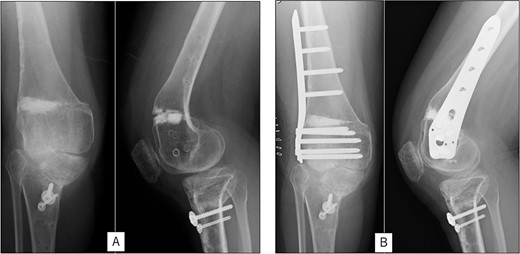

A 23-year-old woman presented with bilateral knee pain and gait abnormalities owing to marked lower extremity deformity. She was diagnosed with EVC as a child but had never been followed up by orthopedics because she was not in pain. On physical examination, marked valgus instability was observed in both knees, and the motion of both knees ranged from 10° to 135°. Radiographic examinations of both knees, including computed tomography, showed valgus deformity, lateral and anterior depression of the proximal lateral tibial plateau, and external rotation deformity of the lower leg. Patellar dislocation was observed in the right knee (Fig. 1). The radiological angles are presented in Table 1. The right knee underwent surgery first, followed by the left 10 months later. Lateral and medial skin incisions were made. Extensive lateral retinacular release, fractional lengthening of the distal lateral hamstring, and Z-lengthening of the iliotibial band were then performed. At this stage, peroneal nerve strain was identified, and decompression of the peroneal nerve was performed. Osteotomy was subsequently performed on the tibia. Closed-wedge varus and derotational osteotomy of the proximal tibia and open-wedge varus osteotomy of the distal femoral varus were performed. In addition, vastus medialis advancement was performed on the right knee, and patellar realignment was achieved in extension (Fig. 2). However, the knee showed a subluxation tendency owing to flexion of >30°; therefore, the postoperative rehabilitation plan progressed more slowly than that of the left knee. Range of motion training began on the left knee immediately after surgery without any restrictions, but on the right knee only after 3 weeks of postoperative immobilization in the extended position. However, ambulation exercise was performed on both knees with no loading for 3 weeks, then partial loading was initiated, and full loading was permitted at 8 weeks postoperatively. Early postoperative standing radiography showed residual mild valgus deformity of the lower limbs (Fig. 2, Table 2). In addition, the right knee showed patellar re-dislocation 2 months postoperatively, and the patellar deformity gradually progressed owing to the femoral implant; therefore, the patient underwent implant removal, tibial tubercle transfer, and medial patellofemoral ligament reconstruction 1.5 years after the initial surgery (Fig. 3). Six months later, she fell while walking and developed a fracture at the osteotomy of the right femur; open reduction and internal fixation were performed (Fig. 4). The remaining years passed uneventfully, and 10 years after the initial surgery, the patient still had mild valgus deformity of the lower limbs, but had no recurrence other than that experienced immediately after surgery, no complaints of knee pain, and a stable gait (Fig. 5, Table 2).

Radiography after right patellar re-dislocation and repair surgery: (A) the patella is eroded owing to contact with the femoral plate. (B) Skyline view after patellar repair surgery. (C) Anteroposterior and lateral view after patellar repair surgery.